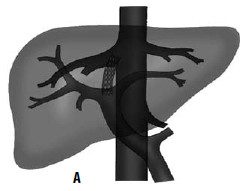

Дистальный спленоренальный анастомоз позволяет сохранить селезенку и не так резко снижает портальное давление, поскольку при этом кровь от воротной вены оттекает через сеть анастомозов и паренхиму селезенки. Такие хирургические вмешательства возможны при отсутствии симптомов печеночной недостаточности, грубых нарушений функционального состояния других органов. При функциональной ограниченности жизненно важных органов и систем целесообразно выполнить декомпрессию портальной системы с помощью чрезъяремного внутрипеченочного порто системного шунтирования (TIPS) (рис. 90). Операция осуществляется по следующей технологии: катетеризируют яремную вену, затем катетер проводят в верхнюю полую и потом в одну из печеночных вен. Далее катетер через ткань печени (перфорируя ее) проводят в одну из портальных вен. Баллонным катетером канал в печени между кавальной и портальной системами расширяют до 6–8 мм и стентируют специальным каркасомстентом.

Рис. 90. Операция чрезъяремного внутрипеченочного портосистемного шунтирования (TIPS): А – схема операции; Б – этап постановки стента; В – контроль проходимости стента